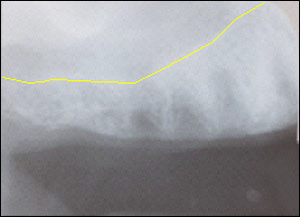

Fig 2: A low maxillary sinus appeared to be an obstacle to implant placement.